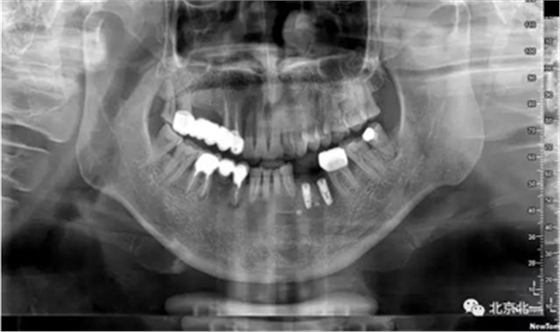

手術(shù)后半年觀察, 成骨良好。